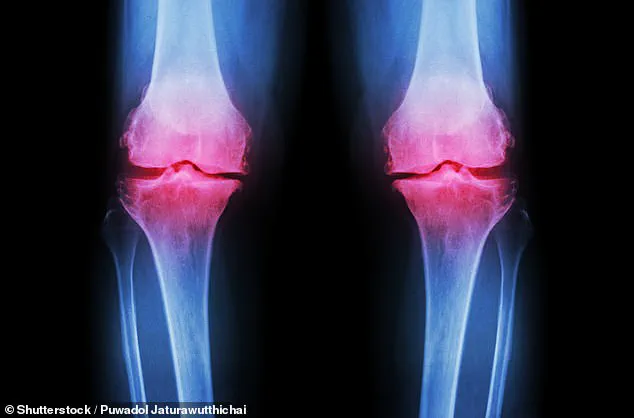

For millions, a persistent ache in the knee is the first sign that something deeper is wrong – a slow loss of movement that can make walking, climbing stairs or even standing painful.

Osteoarthritis, the degenerative joint disease that silently erodes cartilage, is a silent epidemic.

The condition develops when the protective cartilage at the ends of bones gradually breaks down over time, leading to pain, swelling and increasing difficulty moving the joint as bone begins to rub against bone.

Over half of all osteoarthritis cases involve the knees, and with more than 100,000 people a year ending up on NHS waiting lists for knee or hip replacement surgery, the strain on healthcare systems is mounting.